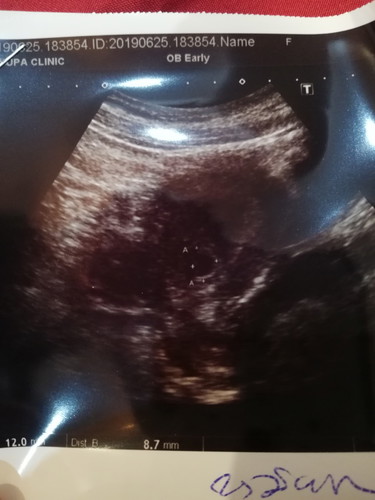

ท้องได้ 6 วีค หมออัลตร้าซาวให้ แต่ไม่เห็นเด็ก

ท้องได้ 6 วีคแล้วคะ เพิ่งไปฝากท้องมา หมอซาวน์ให้ บอกมีแต่ถุงน้ำคร่ำ แต่ยังไม่เห็นเด็ก แล้วแบบนี้จะมีลูกมั้ยคะ กลัวจังเลย? อยากมีลูกมากกก แม่ๆคนไหนเป็นแบบนี้บ้าง ช่วยบอกที ว่าวีคต่อๆมา มีลูกในท้องมั้ยค๊าา (เราท้องแรกช่วยแนะนำที) 30 มิย.62 อัพเดทนะคะ สรุปแล้วตั้งครรภ์ไม่สมบูรณ์ เด็กไม่สร้างตัว แท้งไปแล้ว โดนขูดมดลูกไปแล้ว คะคุณแม่ๆ ขอบคุณทุกกำลังใจนะคะ เสียใจมากๆ